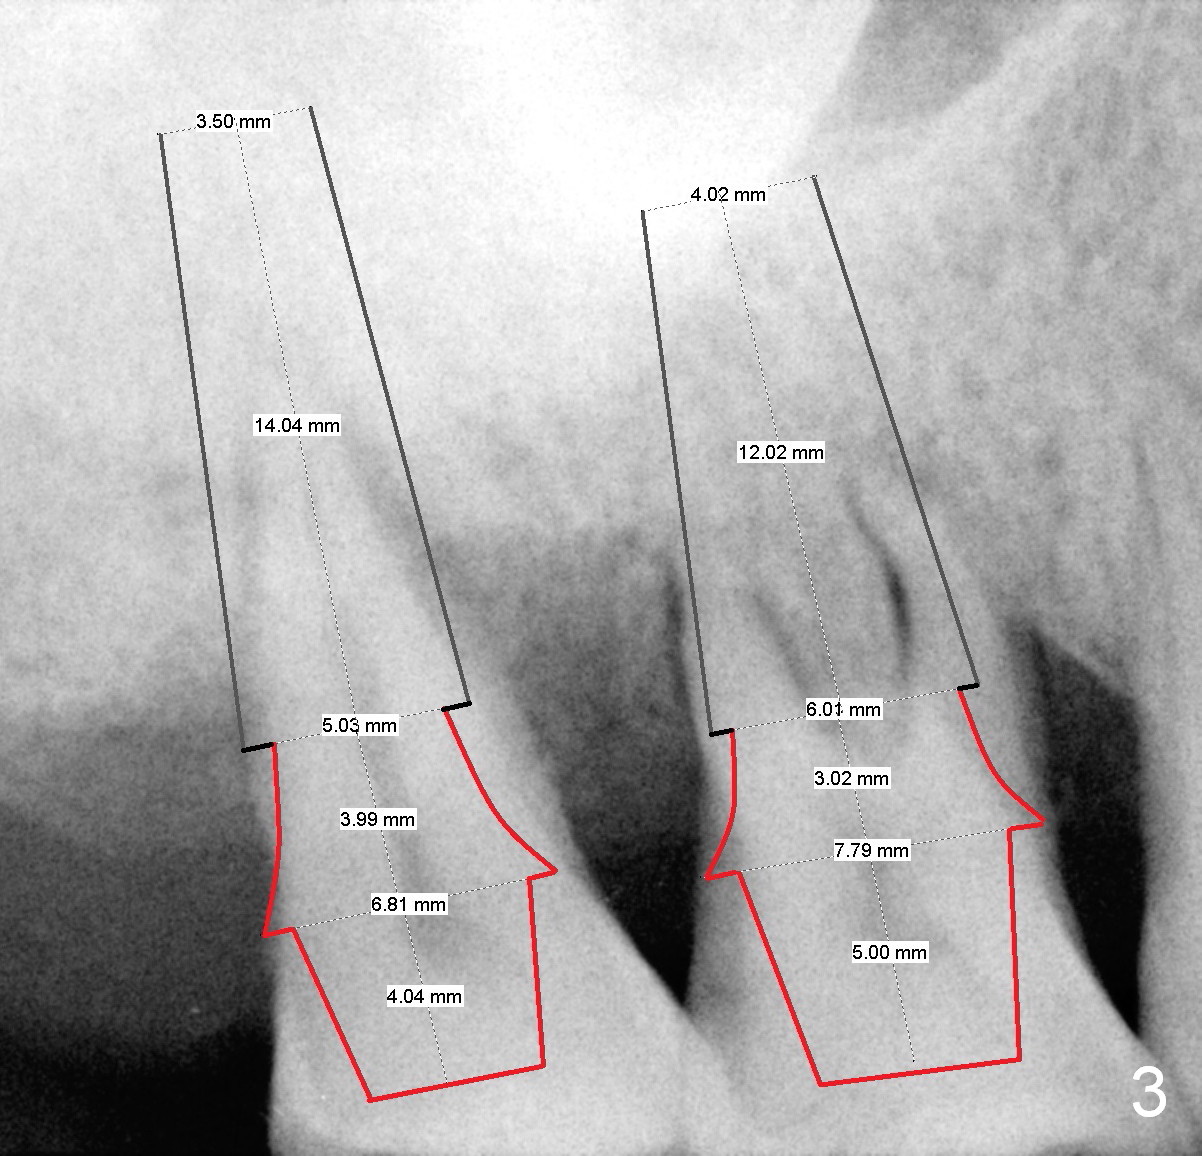

A 52-year-old lady is pleased with the implant at #15 and requests implants at #2 and 3 next (Fig.1,2). Due to severe bone resorption, bone level should be uneven circumferentially. The implants will be placed as apical as possible, i.e., buried in the native bone. If implant threads are exposed in small region, they will be covered by allograft (Fig.3 pink circles). The size of the abutments is shown in red. Clindamycin will be used for socket disinfection.